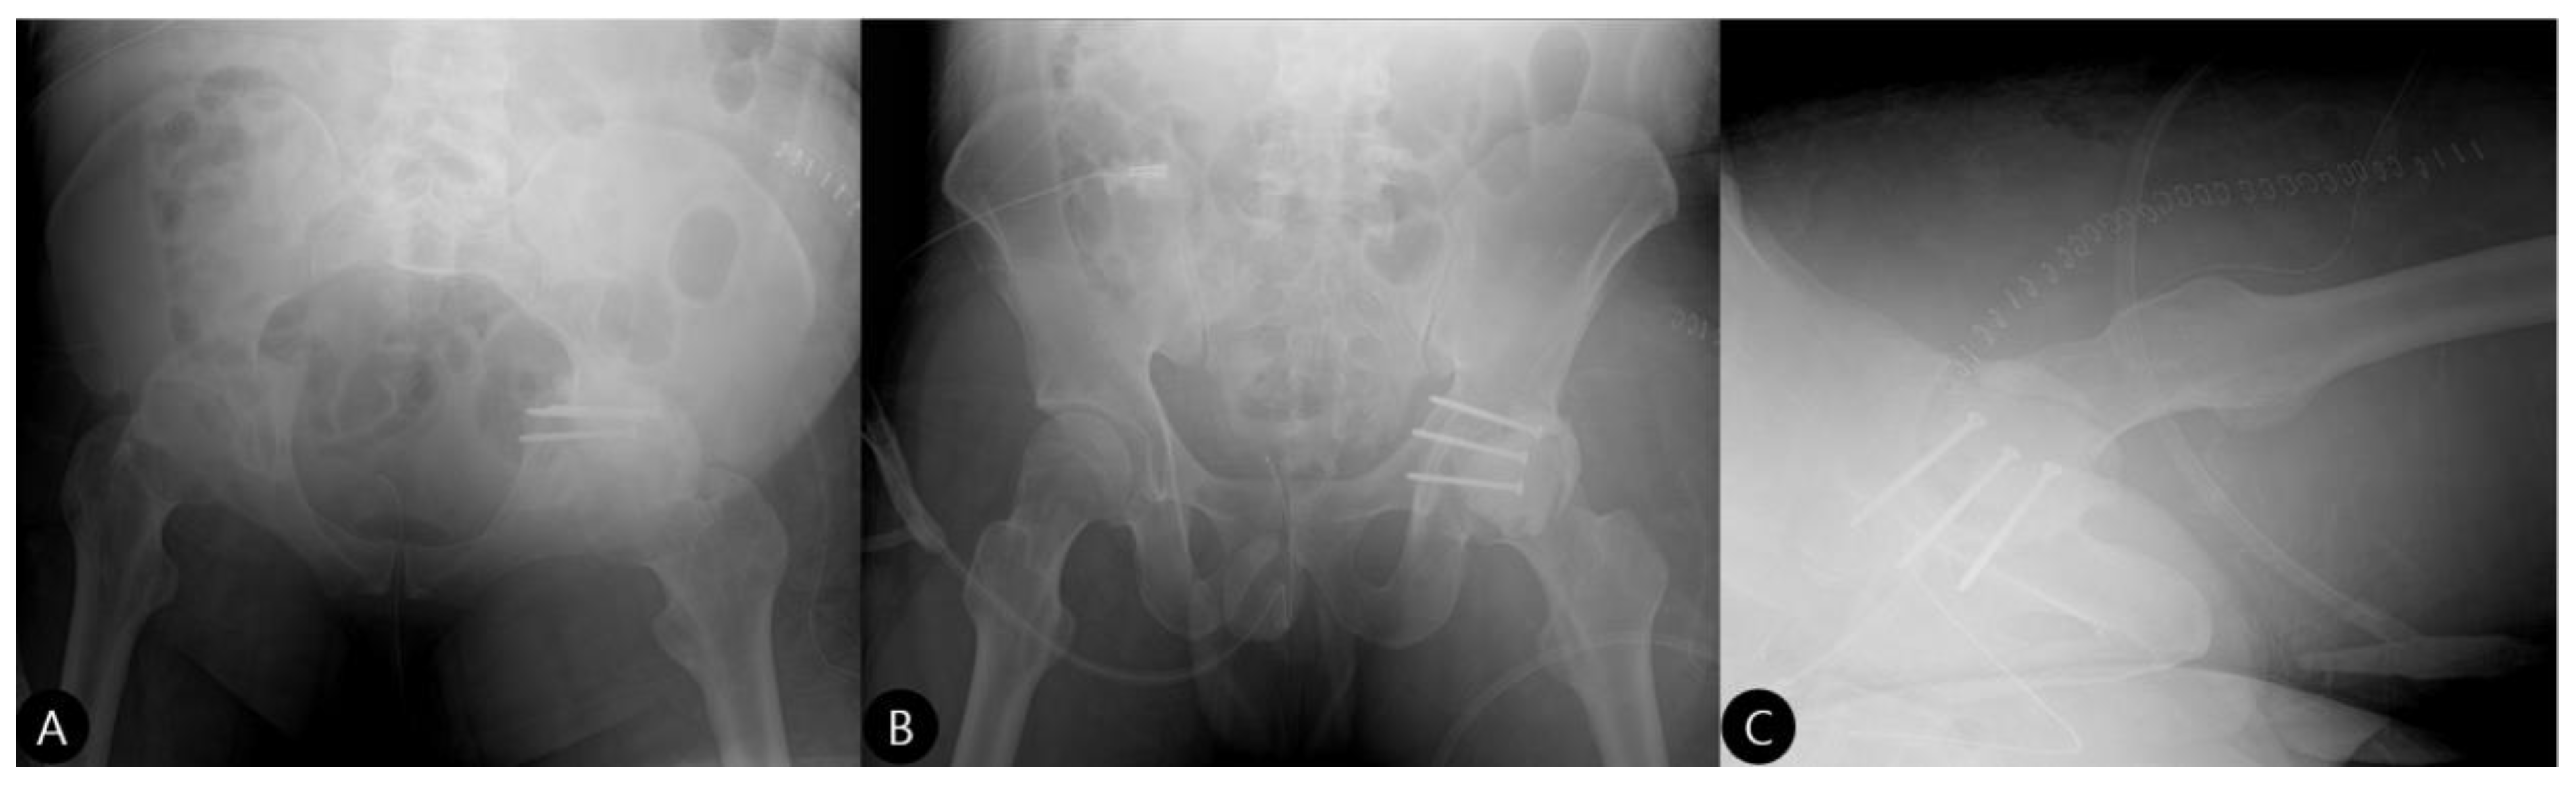

- 3 Months: Radiographs showed a stable hip construct with no signs of subluxation or screw migration (Figure 7). The patient had returned to activities of daily living without major discomfort. The mHHS was 78/100.

- 21 Months: AP pelvic radiographs showed excellent maintenance of joint space and a stable construct without loosening (Figure 9). The patient’s functional outcome was excellent, reporting no pain during daily activities, with only mild discomfort during deep squatting. The mHHS was 85/100.